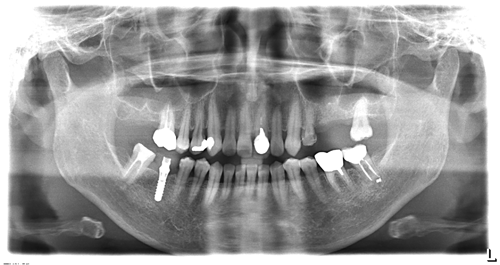

歯周病と根の治療を終わらせた後でインプラントを埋入しました。今では何でも噛めます。